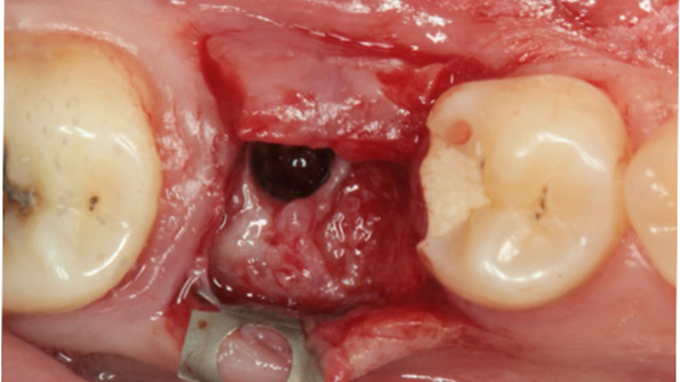

Clinical case: # 46 implant placement & GBR using i-Gen membrane for significant vertical resorption & mixed bone defect

AnyRidge, mandibular posterior, i-Gen, resorption, bone defect, bone regeneration, space management, #46, GBR, Dr. Iulian Filipov

AnyRidge implant system, i-Gen

“AnyRidge KnifeThread achieves excellent stability in regenerated bone & even in only 3mm bone height!”